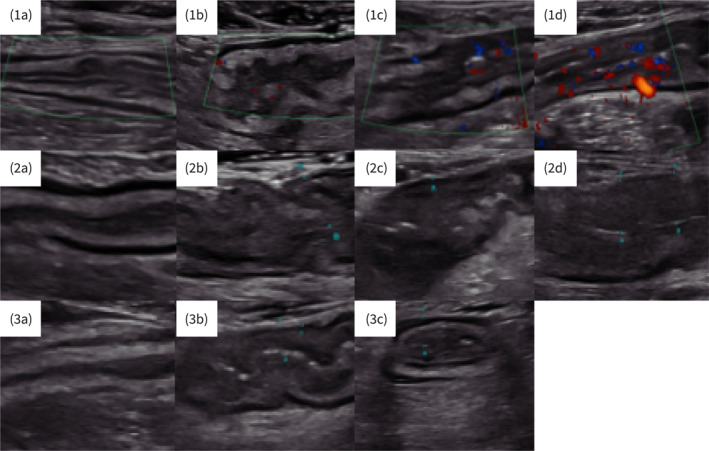

Background: The international bowel ultrasound group-segmental activity score (IBUS-SAS) is a validated tool with high interobserver agreement for accurately detecting disease activity in Crohn's disease (CD). Here, we addressed whether the IBUS-SAS is also suitable to assess disease activity in ulcerative colitis (UC).

Methods: The IBUS-SAS and Limberg scores were determined in the sigmoid colon of patients with UC. The results were correlated to established scores of clinical, endoscopic and histologic disease activity (partial [pMS] and endoscopic [eMS] Mayo-Score, ulcerative colitis endoscopic index of severity [UCEIS], histologic Nancy index) and/or biomarkers of inflammation (C-reactive protein [CRP], fecal calprotectin). Sensitivity, specificity, positive (PPV) and negative predictive values (NPV) for IBUS-SAS and the Limberg score to predict endoscopic and histologic disease activity were computed by receiver operating characteristics (ROC)-analysis.

Results: Fifty-eight patients with UC were enrolled. The median IBUS-SAS was 34.8. It was significantly correlated with pMS, eMS, UCEIS, Nancy index, CRP and fecal calprotectin. On ROC-analysis, a cut-off of 15.9 was reached with 100% sensitivity and 80.0% specificity for the prediction of endoscopic activity, resulting in a PPV of 94.7% and an NPV of 100%. The Limberg score performed only slightly worse (100.0%, 60.0%, 89.9%, 100%, respectively). Comparable results were found regarding the Nancy index for sensitivity (93.9% vs. 93.9%), specificity (57.1% vs. 42.9%), PPV (91.4% vs. 88.9%) and NPV (65.7% vs. 59.0%).

Conclusions: This study highlights the potential of IUS for the non-invasive quantification of disease activity in UC and suggests that the IBUS-SAS should be considered as a diagnostic tool in trials and real-world management of UC.